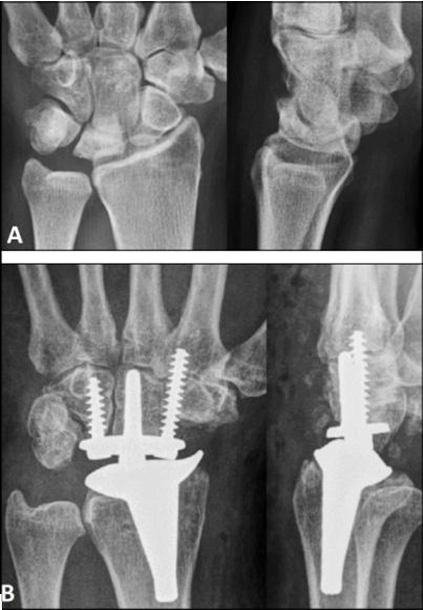

Kienböck’s disease is defined as avascular osteonecrosis of part or all of the lunate, which progresses through several stages if not treated or treated with preservation of the lunate [1][2]. It was first described in 1843 by Peste [3]; and in 1910, Kienböck [4] was the first who recommended to use the term lunatomalacia, and correctly hypothesized that the disease was precipitated by an interruption of the nutrition of the bone as a result of a traumatic insult. However, the etiology is still widely unknown, and many risk factors are discussed such as anatomical features (shape of lunate or distal radius, difference between distal end of radius and ulna, coverage of lunate by radius, arterial factors) and/or repetitive microtrauma potentially leading to subchondral stress fracture [1][5]. Lichtman et al. [6] introduced in 1977 a modified classification with four broad stages which remains the most commonly used today, and stage IIIB, such as in our primarily suggested diagnosis in case presentation, is associated with lunate collapse and fixed scaphoid rotation. The secondary effects of the collapsing lunate are ‘compromised’ wrists including deformity and collapse of the central column, degeneration of the perilunate articulations, proximal row instability, and degeneration of the radial column [5]. For surgical treatment of stage IIIB, the preferred procedures are proximal row carpectomy with a portion ranging from 42–62%, followed by intercarpal fusions with a portion ranging from 11–19%, total wrist fusion with a portion ranging from 2–16%, radial shortening osteotomy with a portion of 12%, vascularized bone grafting with a portion of 6%, trial of splinting with a portion of 4%, and lunate arthroplasty with a portion of 1% [7][8]. An option for surgical treatment of stage IIIA (lunate collapse without scaphoid rotation) is callotasis lengthening of the capitate bone [9]. Another option for treatment of advanced stage of Kienböck’s disease is motion-preserving TWA (Figure 2A B) with a portion of 2% of all TWAs performed by surgeons who have published their experiences with this procedure [10], and the relatively new angle-stable MaestroTM WRS that was used in our case presentation, is one of the modern biaxial-anatomical third generation type that is currently in use [11][12][13][14].

Figure 2: (A) Example for Kienböck's disease stage IIIB with a collapsing lunate in a 54-year-old woman (left wrist), (B) Same patient, treated with another third generation TWA (RE-MOTIONTM Total Wrist).